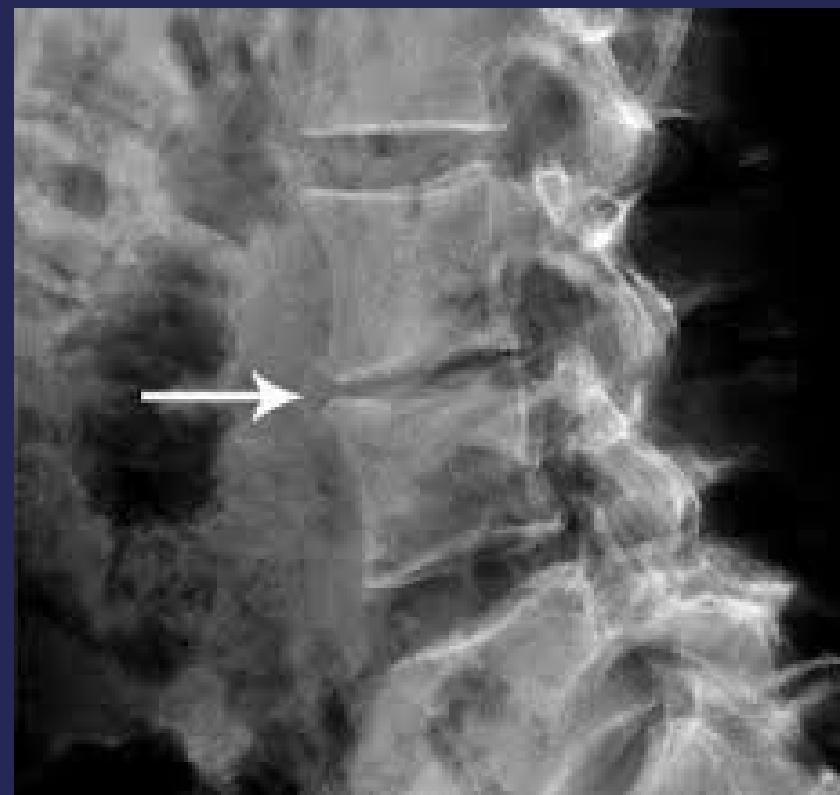

- Imaging: Narrow disc space, soft tissue abscess, angular kyphosis, destruction of 2 adjacent vertebrae with disc space involvement

- MRI: Useful for assessing spinal cord condition